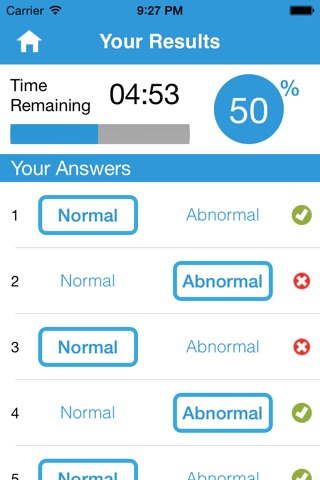

Upon completion of each packet, a results screen displays a percentage score along with specific feedback on each image. The history screen collects data on your most recent attempts in all four topics, enabling you to identify weak points for further study.

Detailed feedback of each test image